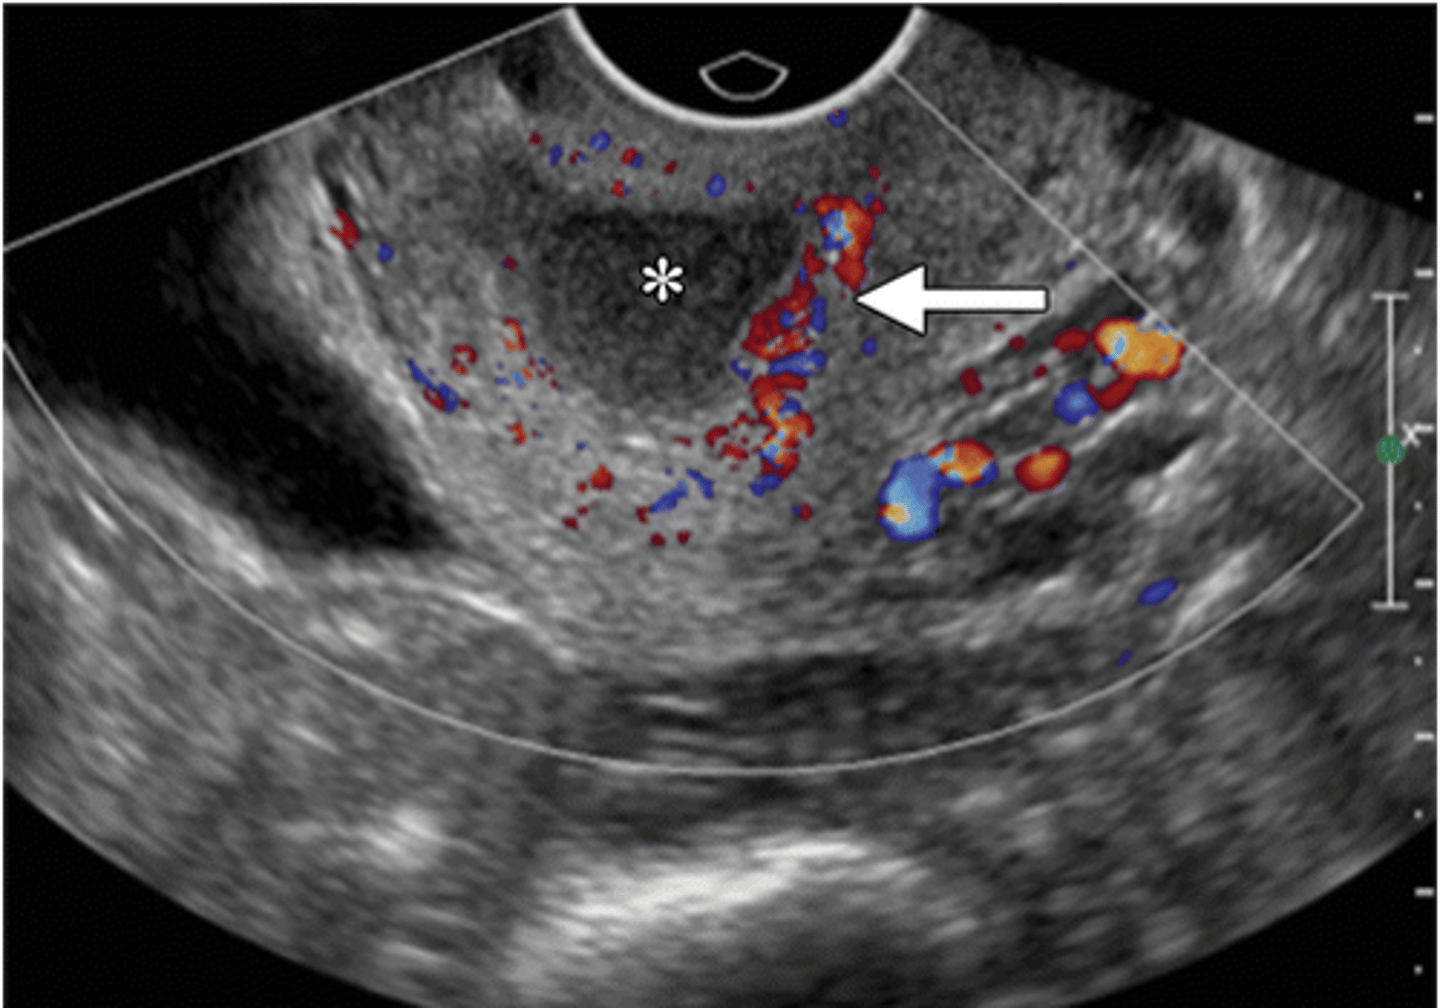

you do a transvaginal sono on your patient with suspected PID. what may you see?

Hyperemia

Dilated uterine cavity

Thickening of the tubes

Fluid in the uterus or tubes

Free-fluid in the pelvis

what does early PID look like

fluid-filled distended endocervical canal (*) with surrounding hyperemia (arrow)